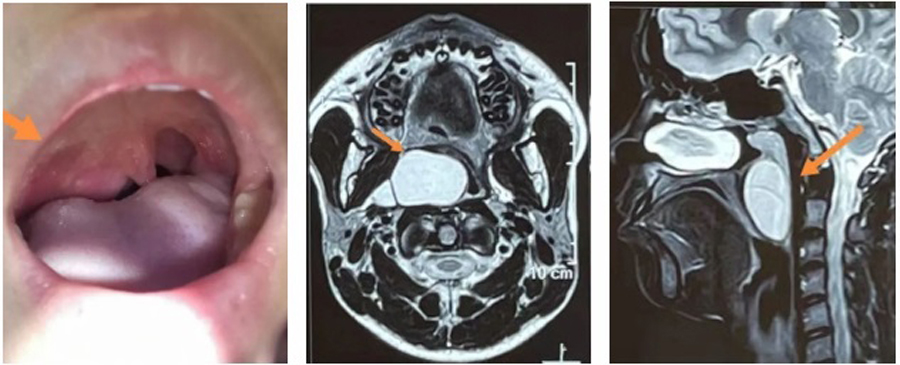

小君因为咽部异物感,右侧面部膨隆来a片网站 就诊,平日并没有咽痛、吞咽困难、消瘦等。在检查中,医生发现,小君右侧软腭明显凸出,边缘可见肿物向内下方膨隆、悬雍垂(小舌头)整体左移、腭弓向内下方偏移,鼻咽镜检查发现肿物上极已达鼻咽部后鼻孔层面,下极到喉部会厌缘平面,跨度大,基地宽。根据小君临床表现,估计肿物生长已数年之久,为明确肿物性质,医生立即进行了进一步检查。通过增强CT、核磁检查明确了肿物的边界,上边界达鼻咽顶、下边界在声门上,外边界与颈外侧动静脉相毗邻、内边界将咽部内侧壁完全向内下方挤压。影像显示肿物边界清晰,结合其临床表现,考虑恶性可能性不大,但由于肿物巨大,向内侧已到中线位置,向外侧,小君的右侧面部已出现略向外膨隆状态,手术迫在眉睫。

确定手术治疗后,张薇副院长和团队根据检查情况,积极制定手术方案。手术最大的风险在于肿物的位置特殊,与颈内动静脉关系紧密,稍有不慎损伤,后果不堪设想。手术入路是经内镜从口咽进入?还是经颈外侧切口进入?张薇副院长仔细分析了手术方案:如果从咽部进入,可以避免皮肤切口造成的颈部瘢痕,但对术者的手术能力要求很高,需要内镜辅助,尽量清除囊壁的同时要注意保护好血管;如果从颈外侧进入,切口较大,造成颈部瘢痕,可能影响患儿颈部美观,甚至影响升学,且手术需跨越整个动静脉区,才能到达肿物的位置,并且有形成咽瘘、神经血管损伤等并发症。为避免颈部巨大瘢痕对患儿的影响,儿医团队还是决定经口咽入路,迎接挑战,尽最大努力,保患儿安康。